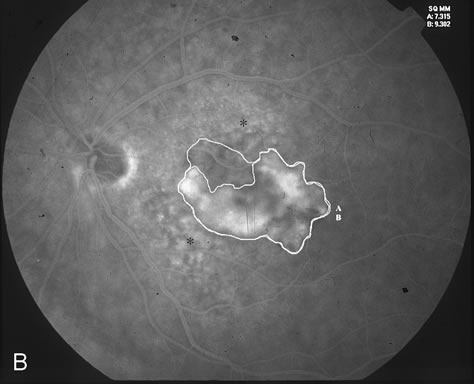

The classic and occult components of CNV are outlined in Figure 2. The percent of the CNV that is classic can then be determined as a proportion of the total CNV. In Figure 2A and B, the area of classic CNV measures 978 square microns and the total lesion measures 11,180 square microns. The classic component is thus 9% of the entire CNV and this lesion is classified as “minimally classic” CNV (defined as less than 50% classic CNV).23,40 The fluorescein angiogram demonstrates another mixed classic and occult CNV lesion in Figure 3. Using digital area measurements, the lesion in Figures 3A and B is composed of 79% classic CNV and fulfils the criteria for predominantly classic, subfoveal CNV that may benefit from verteporfin-PDT based on TAP findings.23,40 The TAP studies also demonstrated a visual benefit in eyes that had prior nonfoveal, thermal laser photocoagulation and subsequent recurrence of CNV below the fovea.23,40 In Figure 4A, subfoveal CNV recurrence in an eye with prior thermal photocoagulation is demonstrated. One month following verteporfin-PDT treatment, Figures 4B (early phase) and 4C (late phase) demonstrate characteristic hypofluorescence of the treated subfoveal CNV on fluorescein angiography.

Fig. 3. A. Fluorescein angiogram reveals predominantly classic CNV. B. Digital imaging outlines the classic component (A) and the entire lesion (classic and occult, marked as B). The area of classic component measures 7,315 square microns. The entire lesion measures 9,302 square microns. The areas marked with an asterisk correspond clinically to drusen. C. Greatest linear dimension (GLD) of the entire classic CNV measures 4,184 microns.